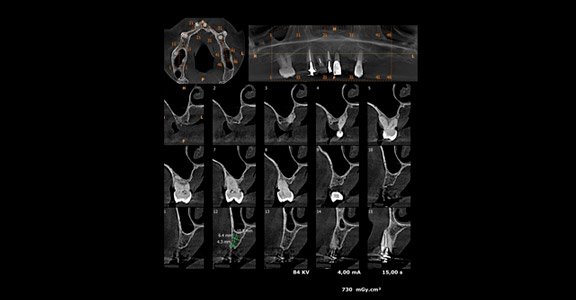

A tomografia computadorizada de feixe cônico (CBCT) é o método de diagnóstico por imagem mais preciso para o planejamento de implantes. Ela é feita com um aparelho semelhante ao de radiografias digitais panorâmicas, que gira 360° e cria imagens a cada grau. O software permite a reconstrução das imagens em 2D ou 3D.

A tomografia computadorizada, atualmente, utiliza feixe cônico que produz uma imagem em formato de cilindro, semelhante aos aparelhos de raio-x que produzem radiografias panorâmicas. Na prática, ela ocorre num escaneamento em 360 graus da região do rosto do paciente. Toda a imagem captada é enviada a um computador, que constrói automaticamente as imagens em 2D ou 3D e elimina as estruturas indesejadas para o planejamento do implante.

A tomografia produz imagens que possibilitam que o profissional realize os cortes precisos na região do osso alveolar. Além disso, ela viabiliza fazer a mensuração da altura e espessura do tecido, tirar as medidas entre o osso e as estruturas adjacentes, como a fossa nasal e os nervos. Sendo assim, é realizado um retrato mais fiel da arcada do paciente, ajudando consideravelmente nos guias cirúrgicos.